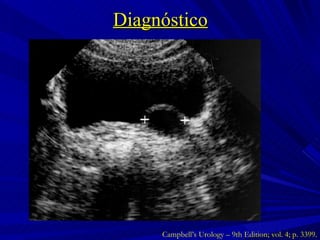

Diagnóstico Campbell’s Urology – 9th Edition; vol. 4; p. 3399.